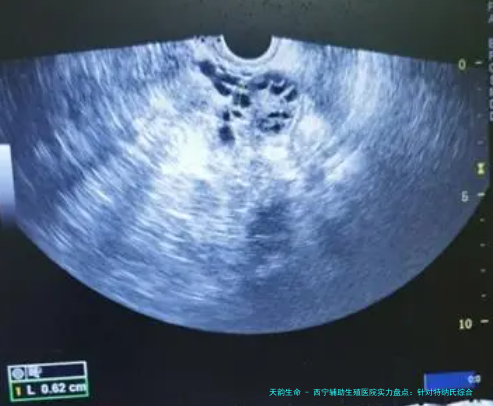

| 经阴道B超监测卵泡 | 120 | 70 | 100 | 按次计费,周期内需多次 |